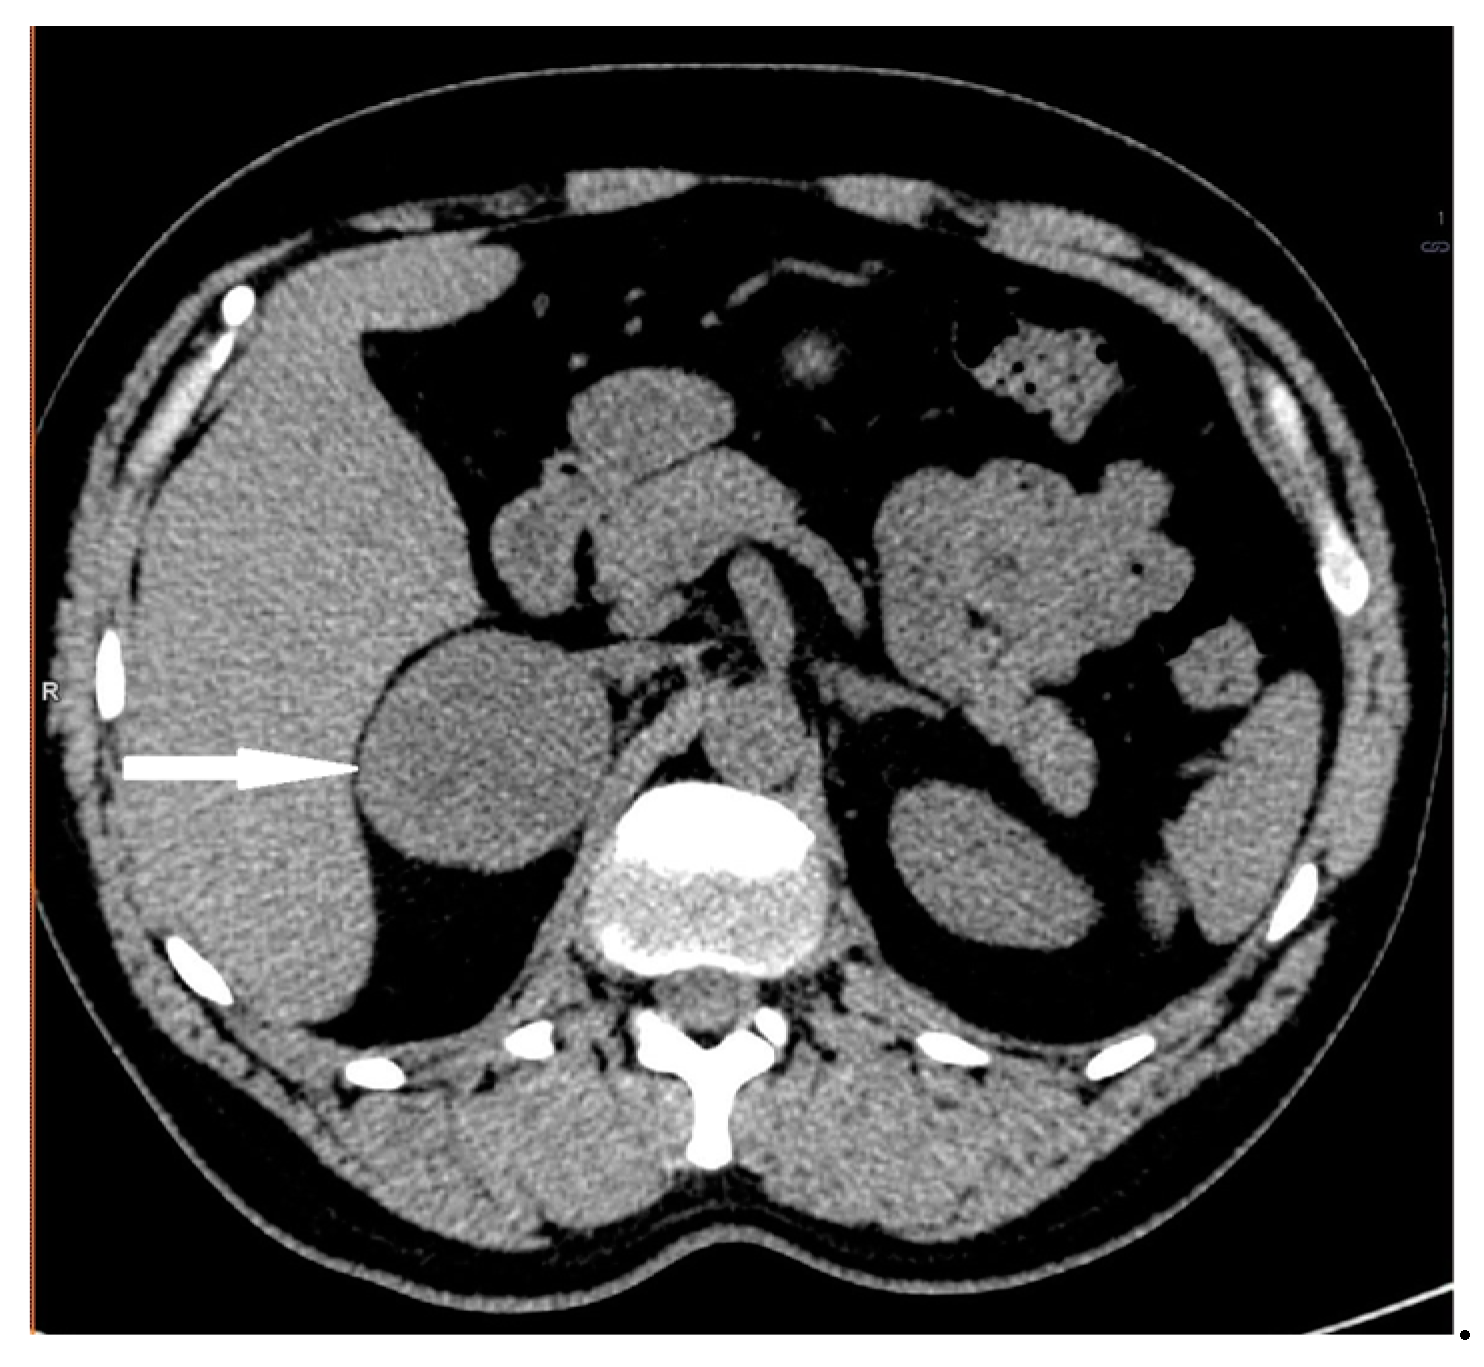

2.2. Case 2